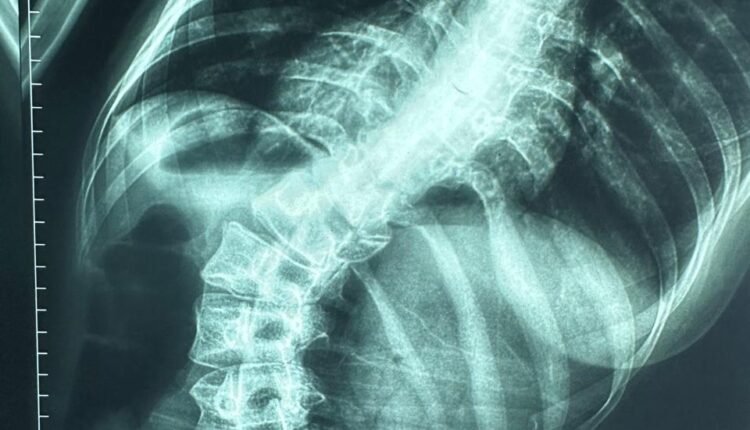

نجح الفريق الطبي بمستشفى قليوب التخصصي في تحقيق إنجاز طبي جديد، وذلك بعد تمكّنه من إجراء عملية دقيقة لمريضة كانت تعاني من اعوجاج شديد بالعمود الفقري، حيث تم إصلاح وتشريح الاعوجاج وتثبيت الفقرات باستخدام 20 مسمارًا معدنيًا لضمان ثبات واستقامة العمود الفقري.